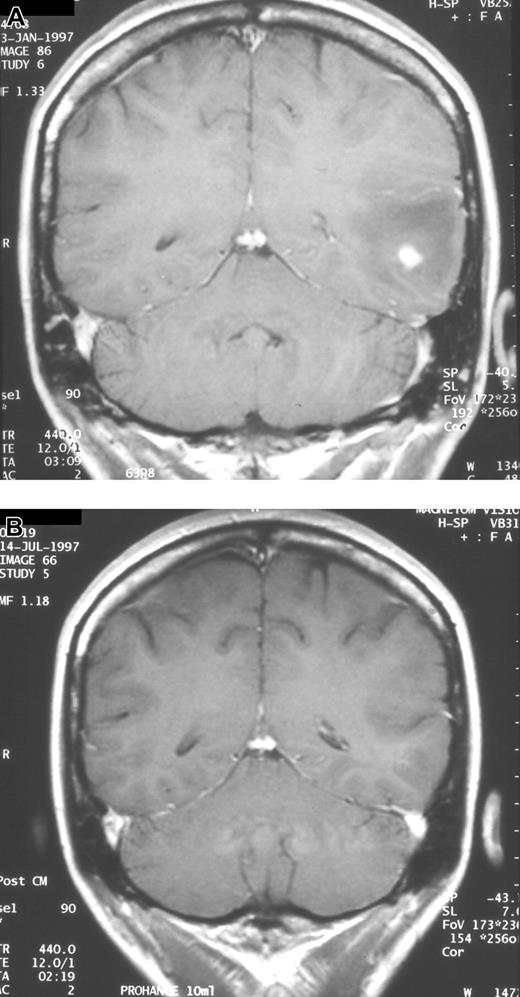

Serial neuroradiologic studies in a patient with CNS aspergillosis. Coronal MRI scans showing complete resolution of a single brain abscess after 133 days of voriconazole therapy. (A) Prior to start of voriconazole. (B) After therapy.